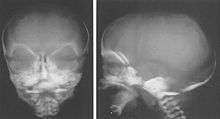

Weaver syndrome (also called Weaver-Smith syndrome) is an extremely rare congenital disorder associated with rapid growth beginning in the prenatal period and continuing through the toddler and youth years. It is characterized by advanced osseous maturation, and distinctive craniofacial, skeletal, and neurological abnormalities.[1] It was first described by Dr. David Weaver in 1974.[2] It is similar to Sotos syndrome.

Children with Weaver syndrome tend to look similar and have distinctive physical and craniofacial characteristics, which may include several, but not all of the following features:

- Macrocephaly

- Large bifrontal diameter

- Flattened occiput

- Long philtrum

- Retrognathia

- Round face in infancy

- Prominent chin crease

- Large ears

- Strabismus

- Hypertelorism

- Epicanthal folds

- Downslanting palpebral fissures